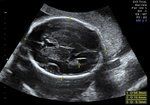

Presentation Scan

- Wellbeing assessment includes position and Presentation of baby and placental position.